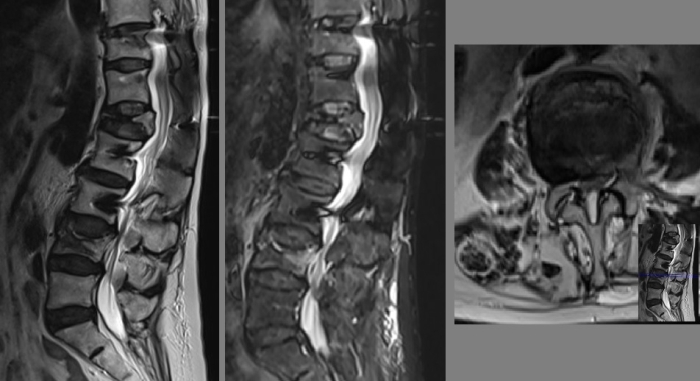

Eski sementli T11-L3 vida sistemi

Resim 1: Hastanın bir ay önce yapılmış olan direkt grafilerinde eski sementli T11-L3 transpediküler vida sistemi görülmekte. L4 korpusu üst endplate'inde kırıkla uyumlu düzensizlik görülüyor.